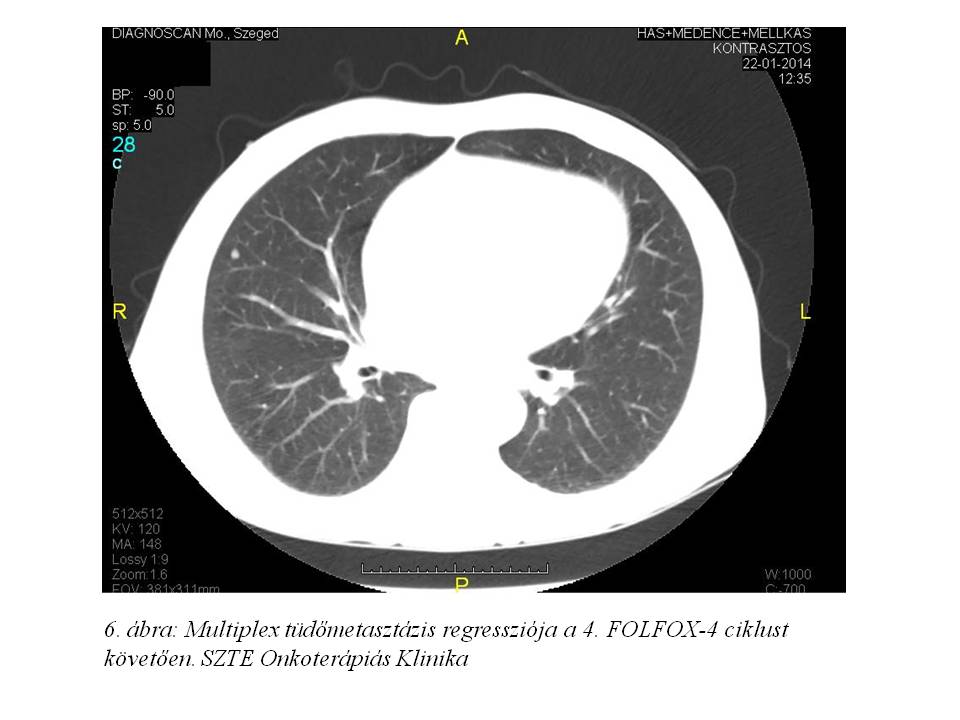

Lokális mellékhatásként postinfúziós phlebitis alakult ki, melyet szteroidos vénakenőccsel kezeltünk. Az első re-staging vizsgálatát a 4. ciklust követően végeztettük: a mellkas, has-kismedence CT vizsgálaton jó regressziót írtak le, a korábbi ascites megszűnt (2014.01.22., 5. ábra, 6. ábra), a tumormarkerek felükre, ill. tizedükre csökkentek: CA 19-9: 59.33 U/ml, CEA: 579 ng/ml. Májfunkciós értékei normalizálódtak, az ALP 1158 U/l-re csökkent.